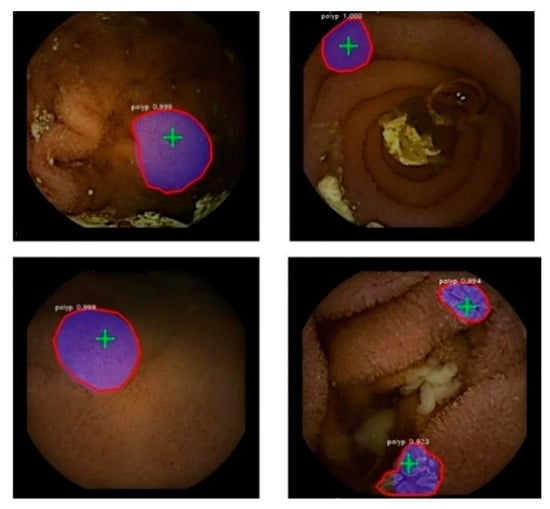

Figure 5 illustrates the ETIS-Larib polyp detection and segmentation results by the proposed model with the ResNet-101 model and pre-trained weights from Flickr’s balloon dataset.

Figure 5.

Polyp segmentation in colonoscopy images (ETIS-Larib). Blue overlay is the predicted segmentation mask. The contour of the ground truth masks is shown in red. Detection points are masked in green.

3.2. WCE Video Analysis

A similar approach is employed for training and testing WCE videos for colonoscopy images, as mentioned earlier. Data augmentation is also applied on the training image dataset for the model to better generalize on different kinds of polyps. The results as shown in Figure 5 indicate the polyp detection and segmentation in the WCE videos. Table 7 illustrates the results from the WCE data. The tabulated values clearly indicate ResNet-101 as the best feature extractor, and the model trained on Flickr’s balloon pre-trained weights is clearly a winner.